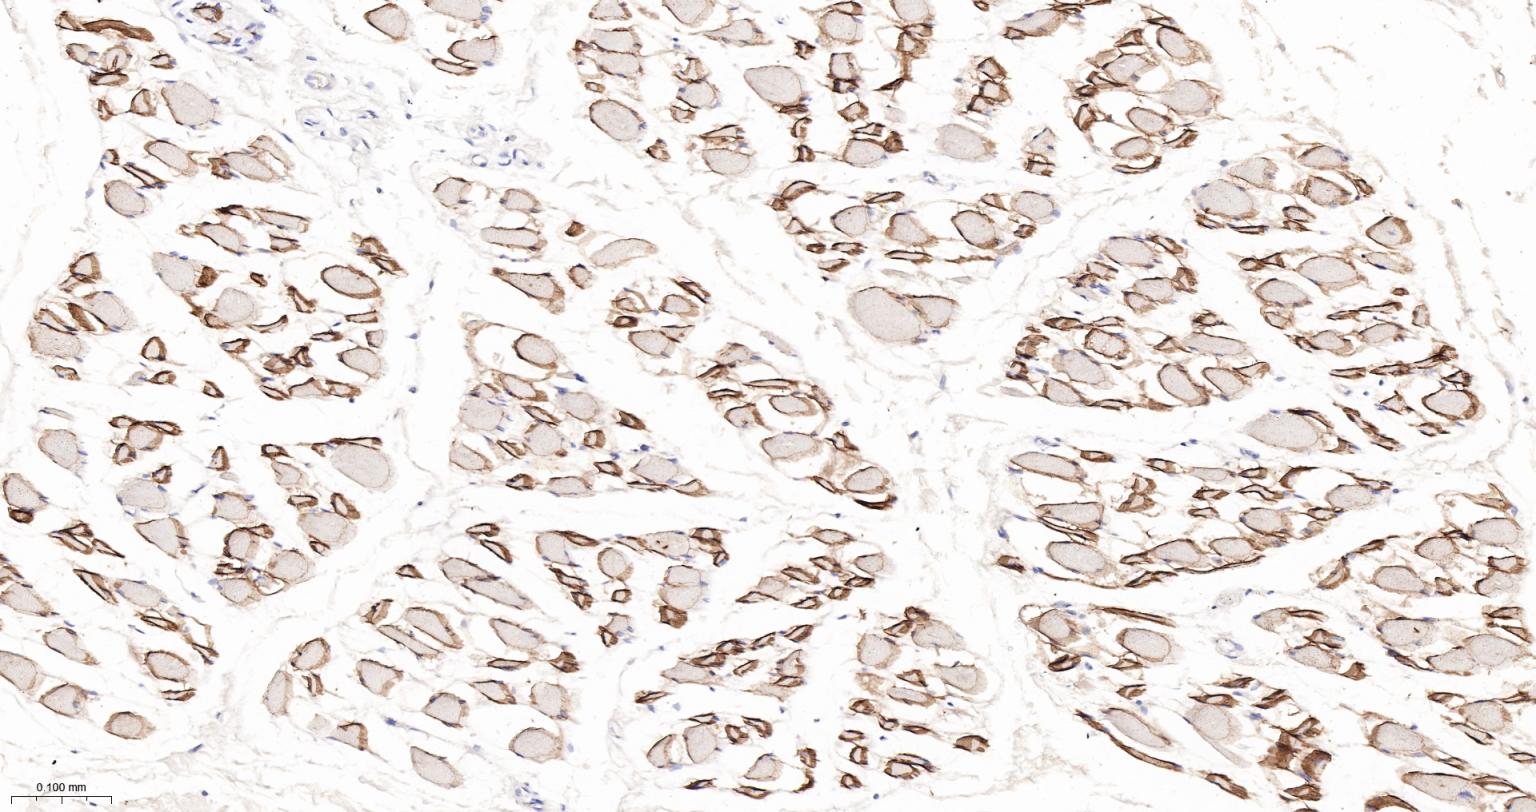

Paraformaldehyde-fixed, paraffin embedded Human Skeletal muscle; Antigen retrieval by boiling in sodium citrate buffer (pH6.0) for 15 min; The section was incubated with alpha Sarcoglycan Monoclonal Antibody, Unconjugated (bsm-61505R) at 1:200 overnight at 4°C, followed by conjugation to the bs-0295G-HRP and DAB (C-0010) staining.

Paraformaldehyde-fixed, paraffin embedded Rat Skeletal muscle; Antigen retrieval by boiling in sodium citrate buffer (pH6.0) for 15 min; The section was incubated with alpha Sarcoglycan Monoclonal Antibody, Unconjugated (bsm-61505R) at 1:200 overnight at 4°C, followed by conjugation to the bs-0295G-HRP and DAB (C-0010) staining.

Paraformaldehyde-fixed, paraffin embedded Mouse Skeletal muscle; Antigen retrieval by boiling in sodium citrate buffer (pH6.0) for 15 min; The section was incubated with alpha Sarcoglycan Monoclonal Antibody, Unconjugated (bsm-61505R) at 1:200 overnight at 4°C, followed by conjugation to the bs-0295G-HRP and DAB (C-0010) staining.